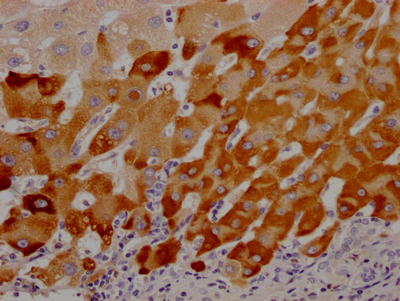

• IHC image of CSB-RA229992A0HU diluted at 1:100 and staining in paraffin-embedded human liver cancer performed on a Leica BondTM system. After dewaxing and hydration, antigen retrieval was mediated by high pressure in a citrate buffer (pH 6.0). Section was blocked with 10% normal goat serum 30min at RT. Then primary antibody (1% BSA) was incubated at 4℃ overnight. The primary is detected by a Goat anti-rabbit IgG polymer labeled by HRP and visualized using 0.05% DAB.